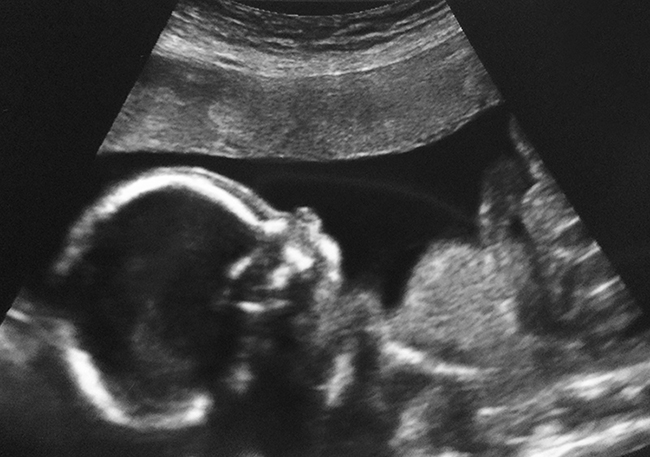

Question about a potty shot / any skull guesses 20wk?

I had my 20wk u/s scan couple of days ago. We're team green, however I'm very curious about the gender. We told the tech we didn't want to find out the gender and she said it's not usually part of the scan anyway (but they usually check it out for you if you ask). But when she took the baby's leg measure, she did it from the potty angle and didn't warn us. My husband looked elsewhere because he really didn't want to know but I looked at the screen. Baby's legs were wide open, but I'm 100% sure I didn't see a penis. There was a very light bump between his/her legs, but for me it looked too low to be testicles, but could've been swollen girl bits. I didn't see any lines (I wasn't looking for them and only realized after the scan that if I'd seen 3 lines it would indicate to a girl). So I don't know if there were lines, but I didn't see a penis either. With our last baby we were shown the potty shot and we could see boy parts very clearly. I'm so confused... Why would she show a potty shot knowing we didn't want to know the gender. I didn't see boy parts but still feel like it's a boy (trying to prepare myself for a third son). Anyone else had a potty shot and not seen a penis, but baby turned out to be a boy anyway?

Here is a profile shot of the baby's skull.